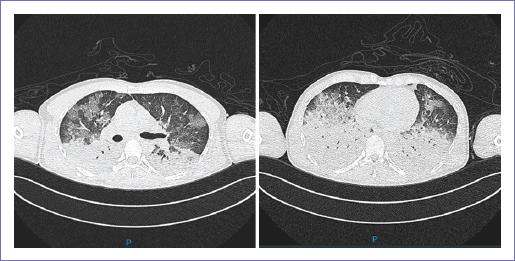

Se trata de un hombre de 37 años de edad originario de Guerrero y residente de la Ciudad de México, profesor de secundaria. Antecedente de hipertensión arterial sistémica de un año de diagnóstico en tratamiento con losartán; diabetes mellitus tipo 2 de 1 año de diagnóstico tratada con sitagliptina. Gastropatía crónica de origen biliar con esofagitis, diagnosticada por endoscopia, pérdida de peso de 25 kg en 18 meses. Es referido a nuestra unidad por hallazgo incidental de tumor dependiente de glándula suprarrenal izquierda por tomografía de abdomen (Fig. 2). Se solicitaron marcadores funcionales: corticotropina, hormona adrenocorticotrópica plasmática, cortisol plasmático, aldosterona sérica, adrenalina sérica, noradrenalina sérica y ácido vanilmandélico en orina, los cuales no fue posible realizar por falta de recursos en la unidad. A la exploración física, sin actividad tumoral palpable, ni signos clínicos de síndrome de Cushing. Durante su internamiento, presentó deterioro del estado de alerta y descompensación hemodinámica súbita, taquicardia, taquipnea, hipotensión sostenida e insuficiencia cardiaca, por lo que se decide manejo avanzado de la vía aérea y colocación de catéter venoso central para iniciar apoyo vasopresor. Por el deterioro súbito, se realizó angiotomografía, que evidenció zonas de consolidación pulmonar bilateral (Fig. 3). Se ingresó a terapia intensiva con doble apoyo vasopresor, norepinefrina y vasopresina, para obtener tensiones arteriales perfusorias, logrando de manera parcial estabilidad hemodinámica.

Figura 3 Tomografía computarizada de tórax, realizada una hora después del inicio de descompensación hemodinámica donde se observan zonas de consolidación en ambas bases pulmonares y zonas en vidrio despulido en los segmentos anteriores.